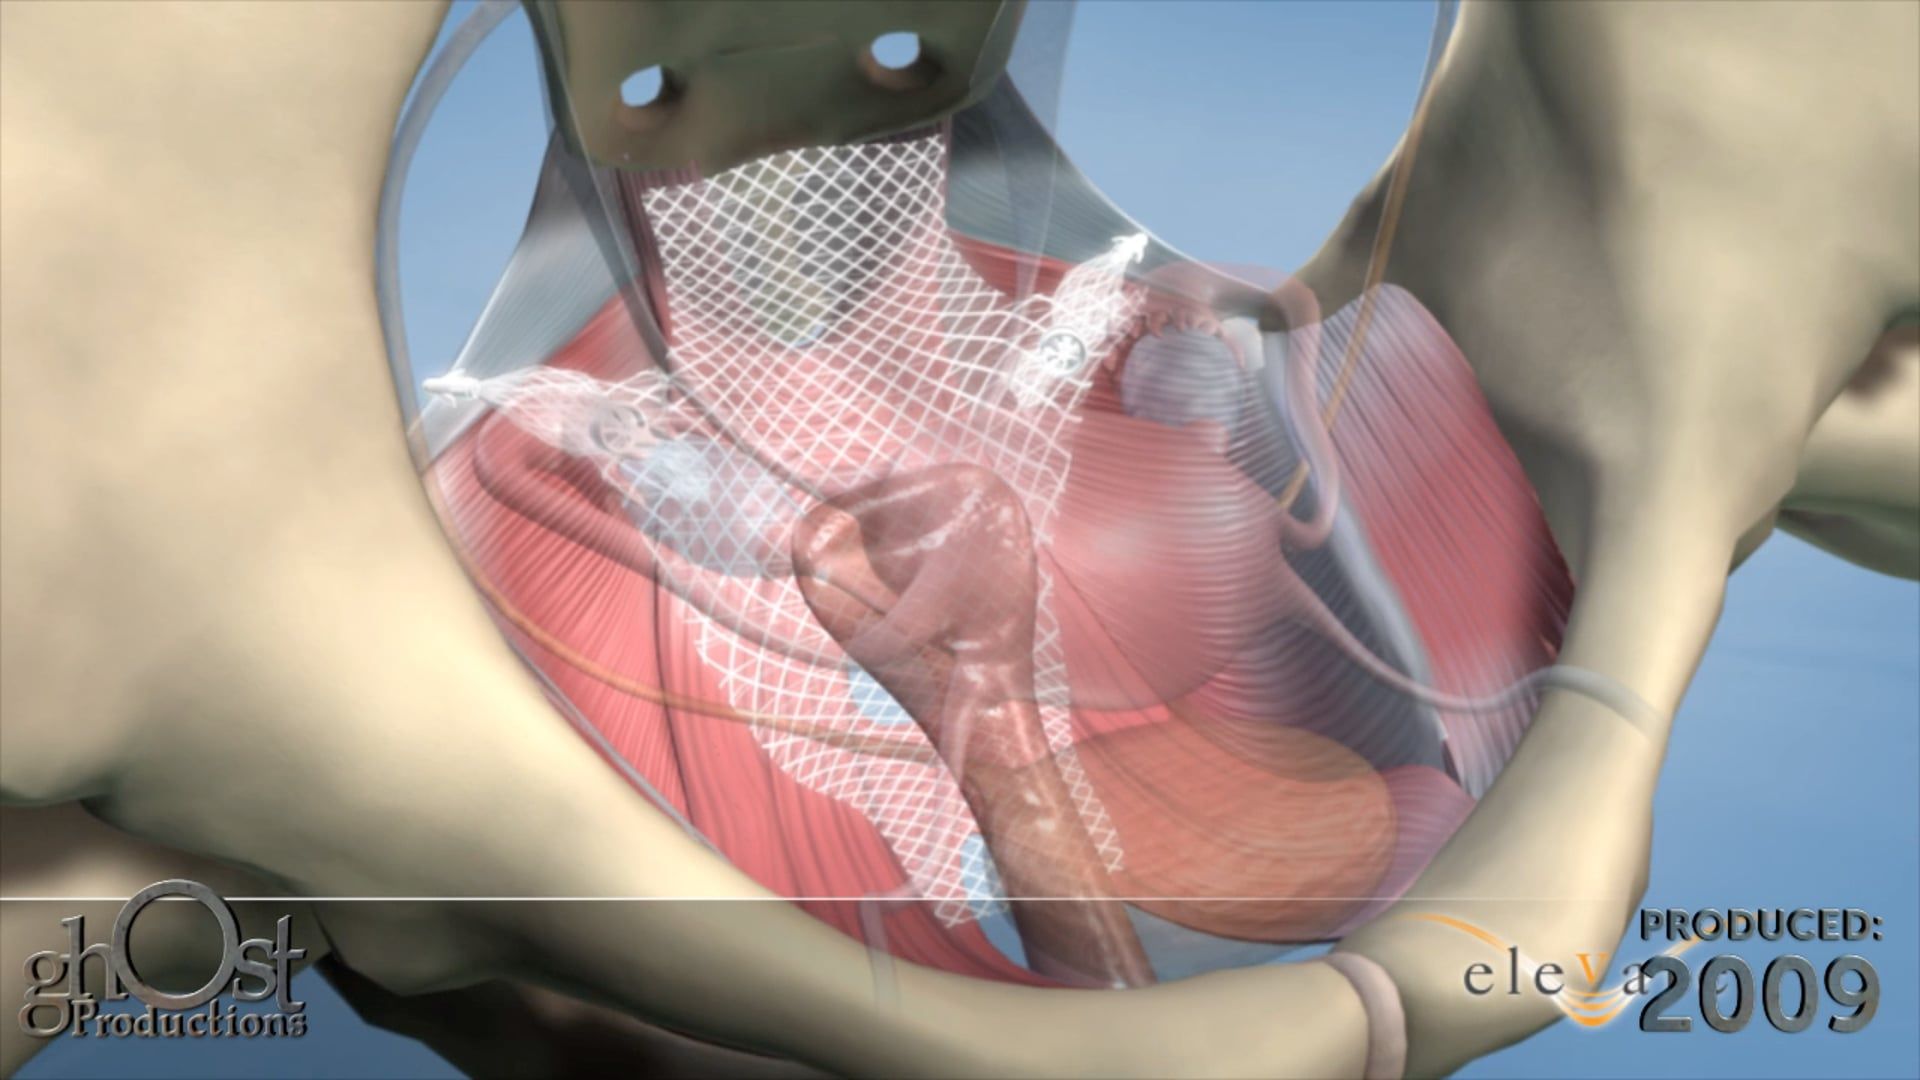

Discover the AMS Continuum, a reliable and innovative bladder anchored urinary catheter with retractable tines, through this stunning animation.

Looking for a reliable and effective bladder anchored urinary catheter with retractable tines? Look no further than the AMS Continuum, brought to life in stunning detail in this animation from Ghost Productions. Our team worked closely with American Medical Systems to create a visual representation of this innovative medical device, highlighting its unique features and benefits. Whether you're a healthcare provider looking for the latest in urinary catheter technology or a patient seeking a more comfortable and secure solution, the AMS Continuum is a game-changer. Watch our animation today to learn more!